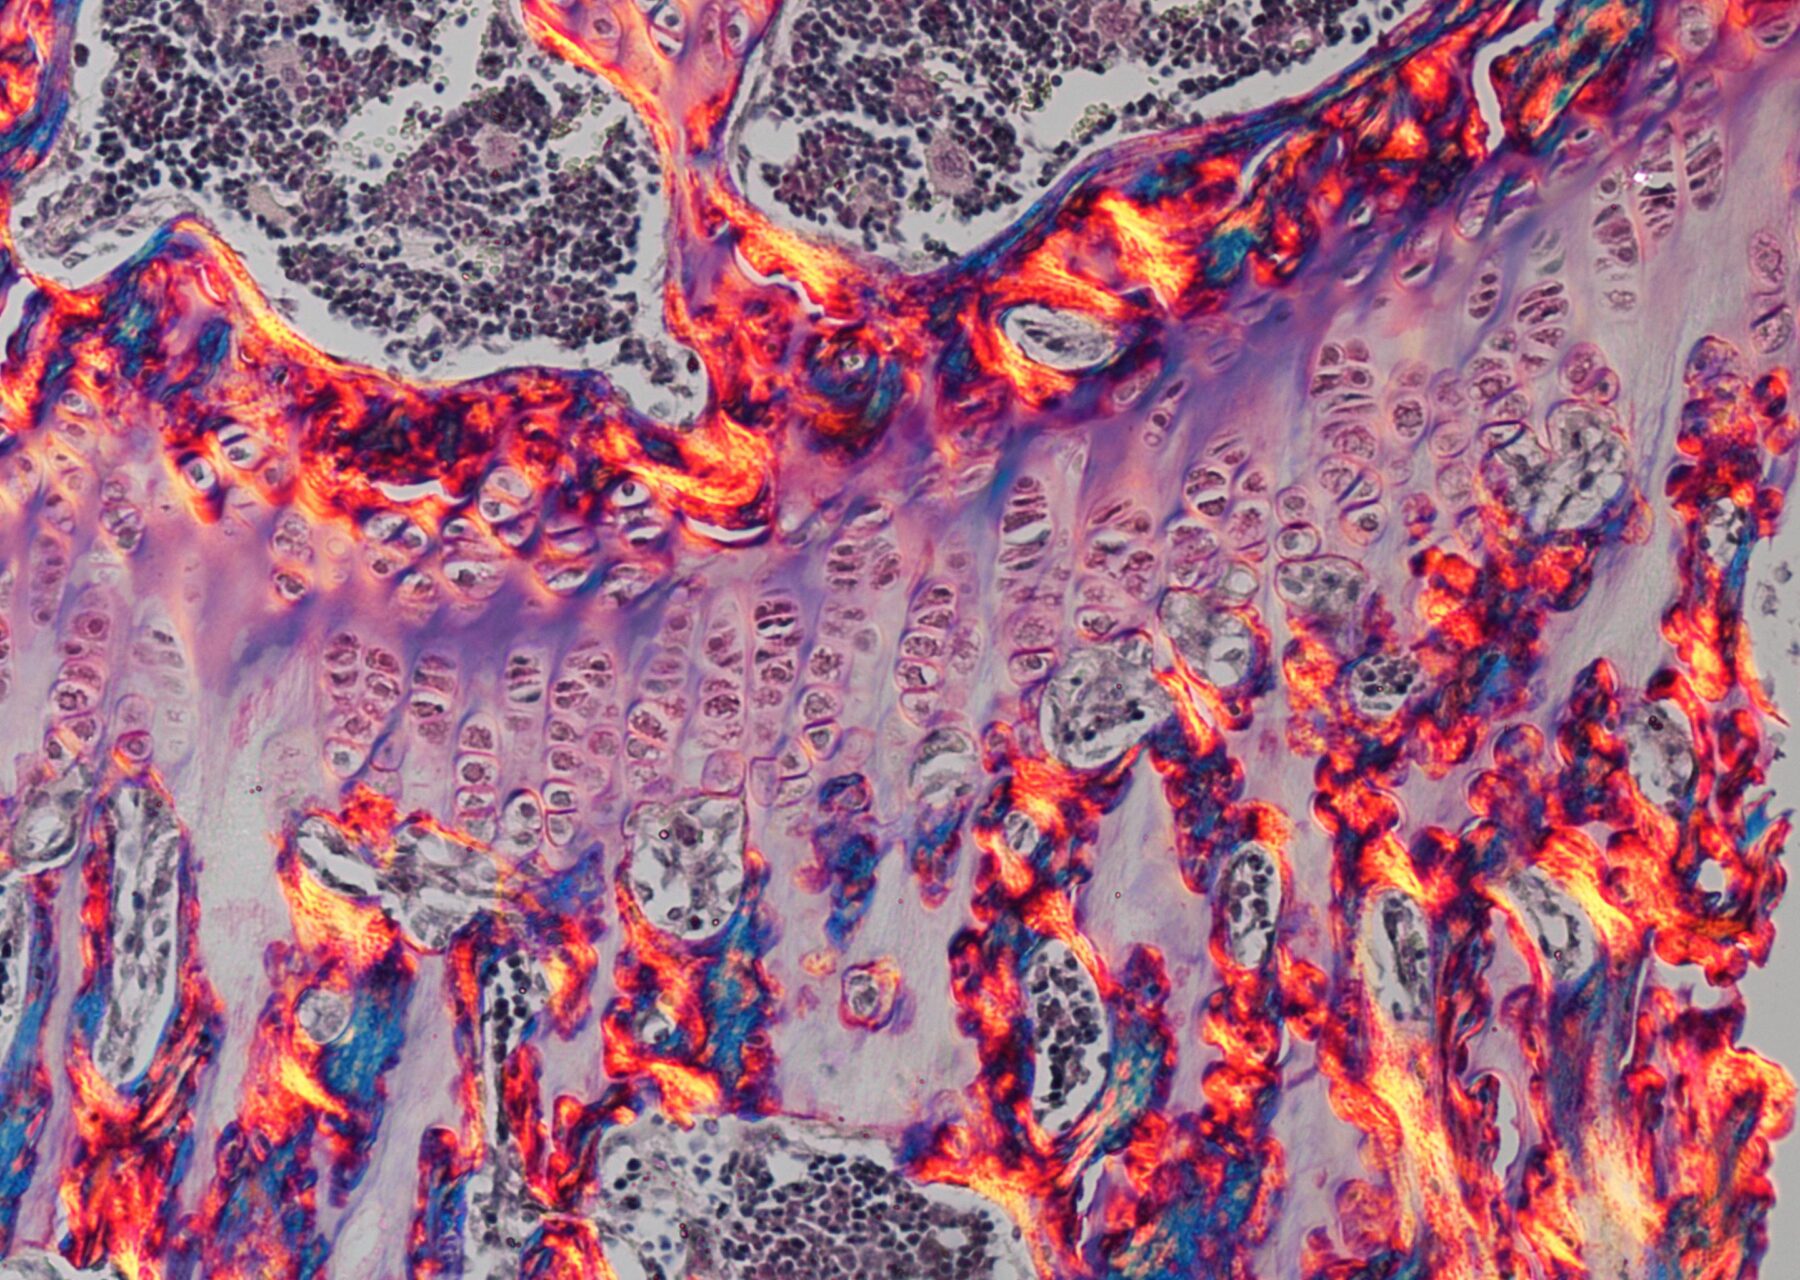

Our Research is beautiful image campaign highlights images that showcase your research – from your science, to the people in your lab and everything that surrounds it.| Cancer Research UK - Cancer News

After a difficult time picking a winner, here are a few of our top picks from the rest of February's entries.| Cancer Research UK - Cancer News

Our Research is Beautiful campaign continues to inspire with some fantastic images, but there has to be a winner, and here’s February’s…| Cancer Research UK - Cancer News

Our Research is Beautiful campaign continues to inspire with some fantastic images, but there has to be a winner, and here’s January’s…| Cancer Research UK - Cancer News